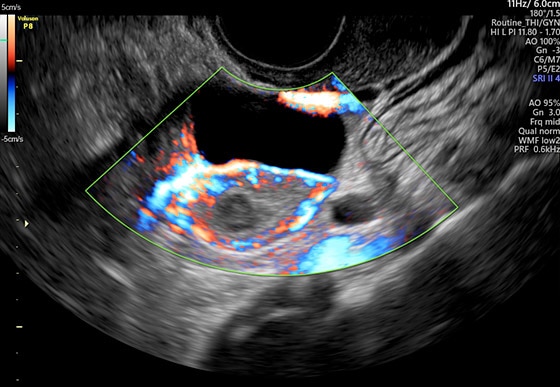

- Усовершенствованное цветовое допплеровское картирование — для более детального исследования анатомии и функционального состояния сосудистой системы.

- Высокочувствительный цветовой допплер.

Максимум клинической информации на одном изображении благодаря широкому сектору сканирования на конвексных и внутриполостных датчиках.